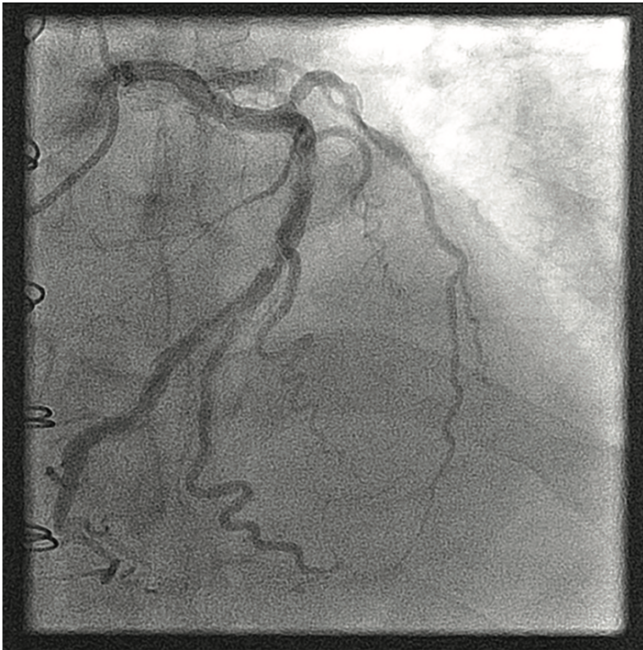

A 61-year-old man with a past history of coronary artery disease with single-vessel bypass surgery 5 years ago (saphenous vein graft [SVG] to the left anterior descending [LAD] artery), hypertension, cardiomyopathy with baseline ejection fraction (EF) 15-20%, end-stage renal disease on nightly peritoneal dialysis, anemia (hemoglobin [Hb] 7.5 g/dL, baseline 9.6 g/dL) presented to the emergency department with 3 days history of chest pain. He was on dual antiplatelet therapy including aspirin and clopidogrel. Cardiac biomarkers were elevated and upended to a peak troponin I of 0.15 ng/mL (normal values). He was transfused with 2 units of packed red blood cells and his repeat Hb was 8.4 g/dL (inappropriate response). However, there were no active signs of bleeding. He continued to have chest discomfort and was referred for left heart catheterization.